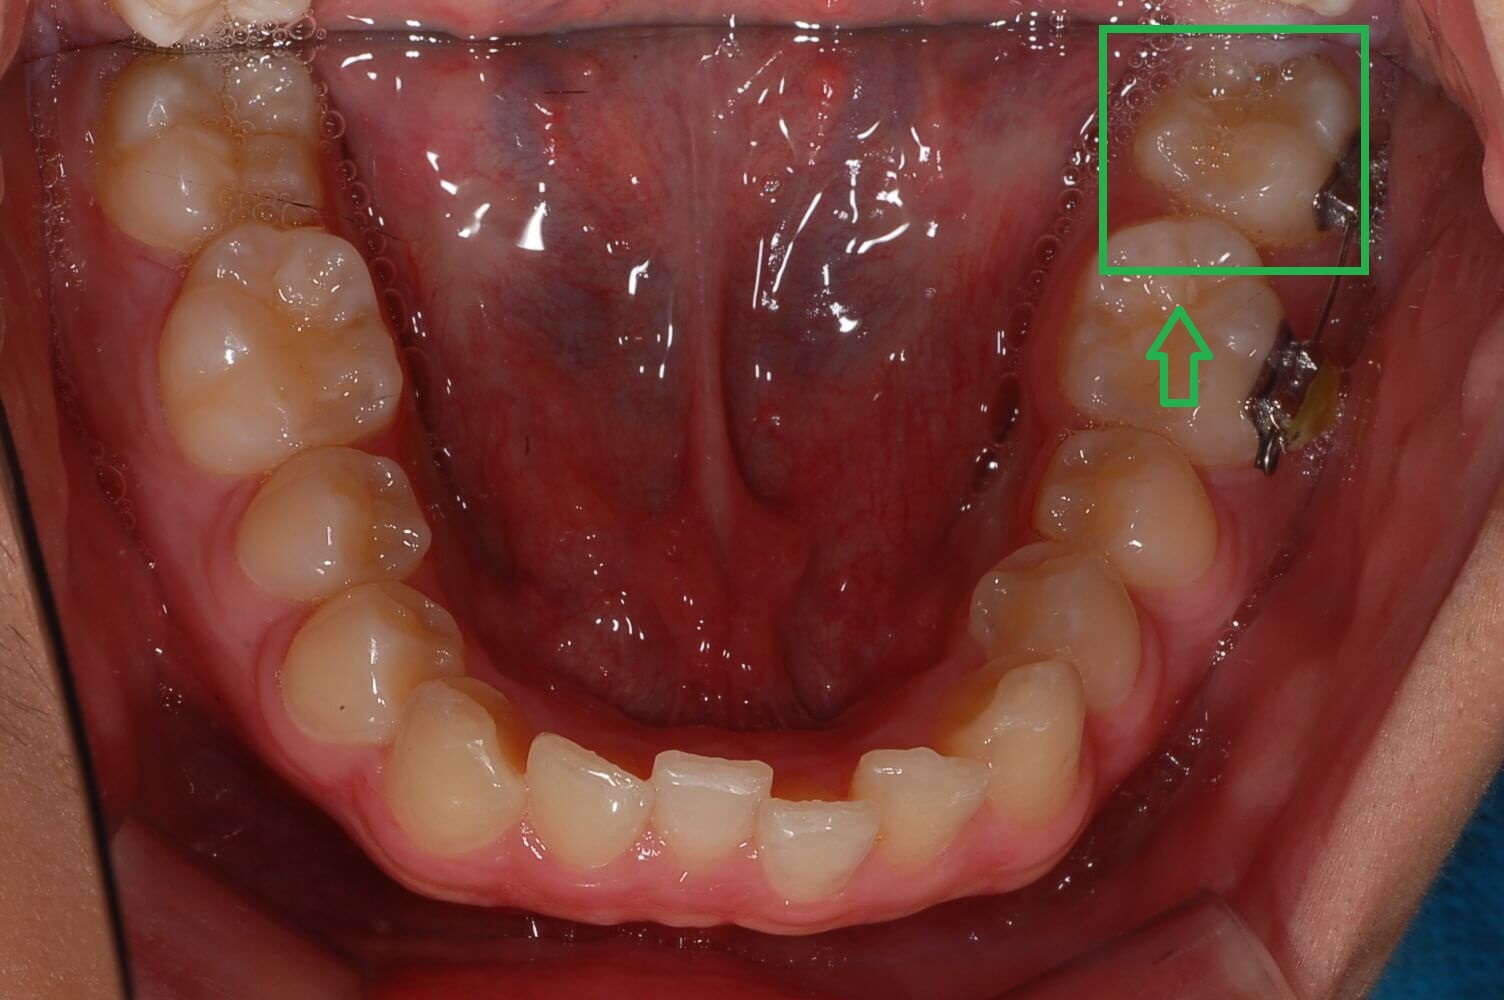

2. 가위교합 교정실시 (3개월 상태)

사진을 보시면 거의 정상으로 돌아왔습니다. 사실 이때 이 정도면 그냥 살아도 되지 않나 하는 생각도 해보았습니다.

하지만 이 상태로 두면 치아는 복원력이 강해 다시 누울 수 있고 어금니가 일어섬으로써 다른 치아들과 맞물리는 높이가 맞지 않아 더 큰 문제 발생된다는 것을 알았습니다.

윗 어금니는 생각보다 제자리에 돌아오는 속도가 늦었으나 전체 블라켓을 설치하고 과개교합 교정에 들어갔습니다.

▼ 3개월 후 어금니 가위교합 교정상태(아래 어금니)

▼ 3개월후 어금니 가위교합 교정상태(윗 어금니)